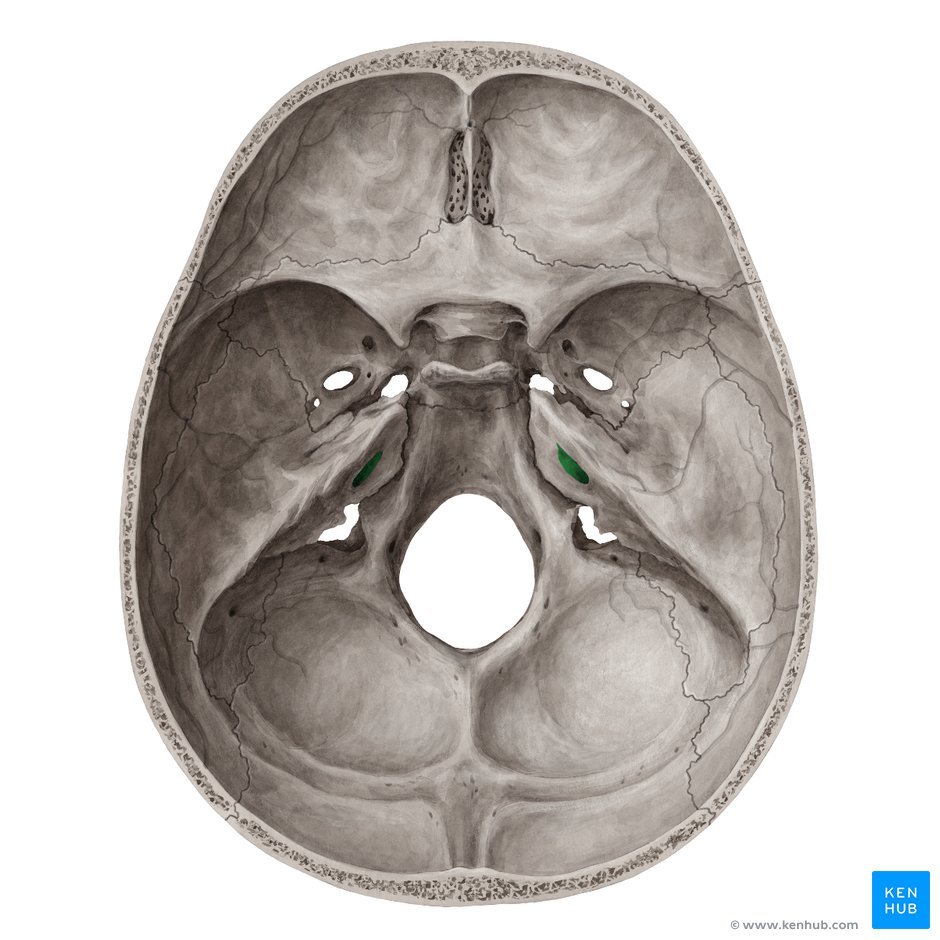

which foramen is this?

foramen ovale

foramen spinosum

Internal acoustic meatus

Foramen lacerum

Carotid canal

The internal carotid artery enters the skull via the [] this is an oblique channel through the skull base.

It then emerges above foramen [].

The internal carotid artery enters the skull via the carotid canal, this is an oblique channel through the skull base.

It then emerges above foramen lacerum.

The middle meningeal artery is a small artery which enters the skull through foramen [] and travels inside the skull passing deep the [].

The middle meningeal artery is a small artery which enters the skull through foramen spinosum and travels inside the skull passing deep the pterion.